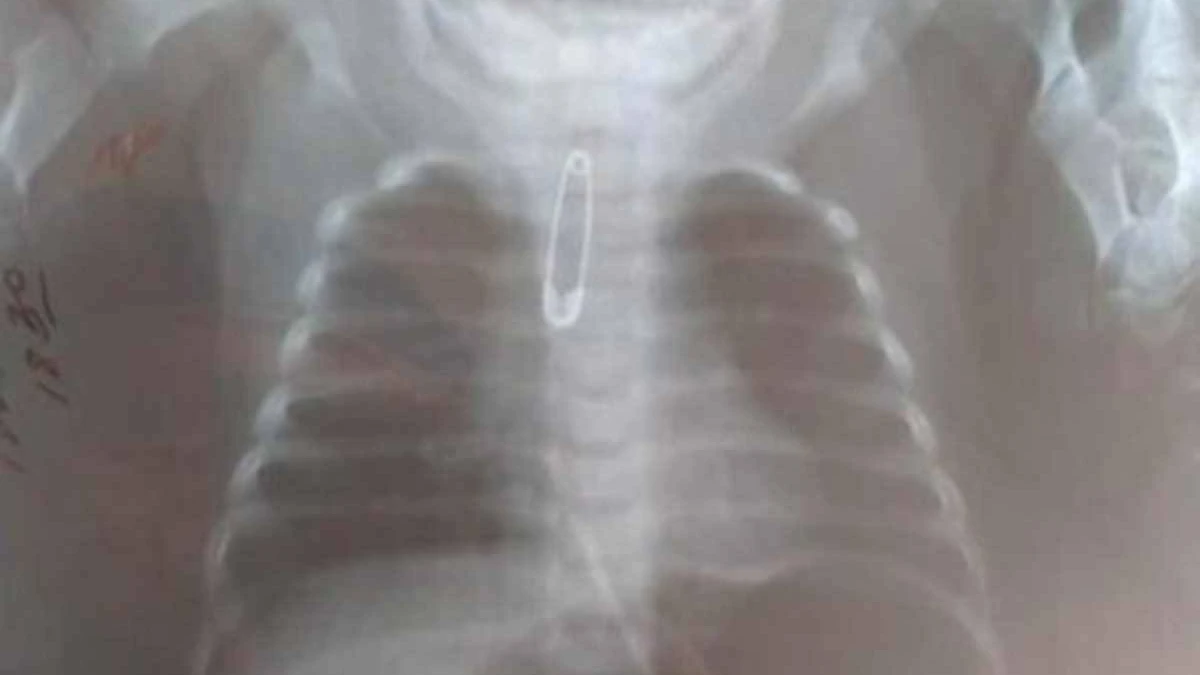

Нәрестені шұғыл түрде тексерген дәрігерлер рентгенограмма жасаған. Тексеру қорытындысында трахеяның жоғарғы үштен бір бөлігінде түйрегіш анықталды.